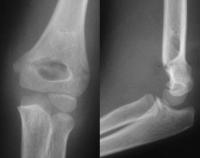

Radiographie

On demande une radiographie du coude Face et Profil

Le trait est transversal, extra-articulaire.

En fonction de l’importance du déplacement, on détermine le type de la fracture (classification de Lagrange et Rigault) :

- Stade 1 : fracture non déplacée, seule la corticale antérieure est touchée

- Stade 2 : bascule postérieure peu importante, les 2 corticales sont rompues

- Stade 3 : bascule importante mais les 2 fragments restent en contact

- Stade 4 : bascule importante, les 2 fragments ont perdu tout contact